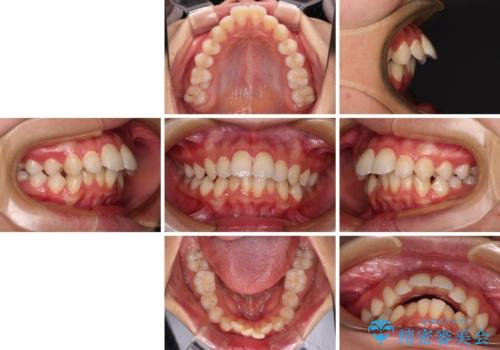

指が入るくらいに隙間のある上下前歯 抜歯矯正で横顔の印象が大きく改善

- 上顎前歯の突出感を気にして来院された患者様です。

舌の突出癖などにより、上下前歯の間に指が入るくらい隙間のできる状態でした。

下顎は叢生があったため、上下左右の第一小臼歯4本を抜歯し、更には口元の突出感を大きく改善させるために、上顎臼歯を後方に移動させるための補助装置をしようし、ワイヤー装置にて矯正治療を行うこととしました。